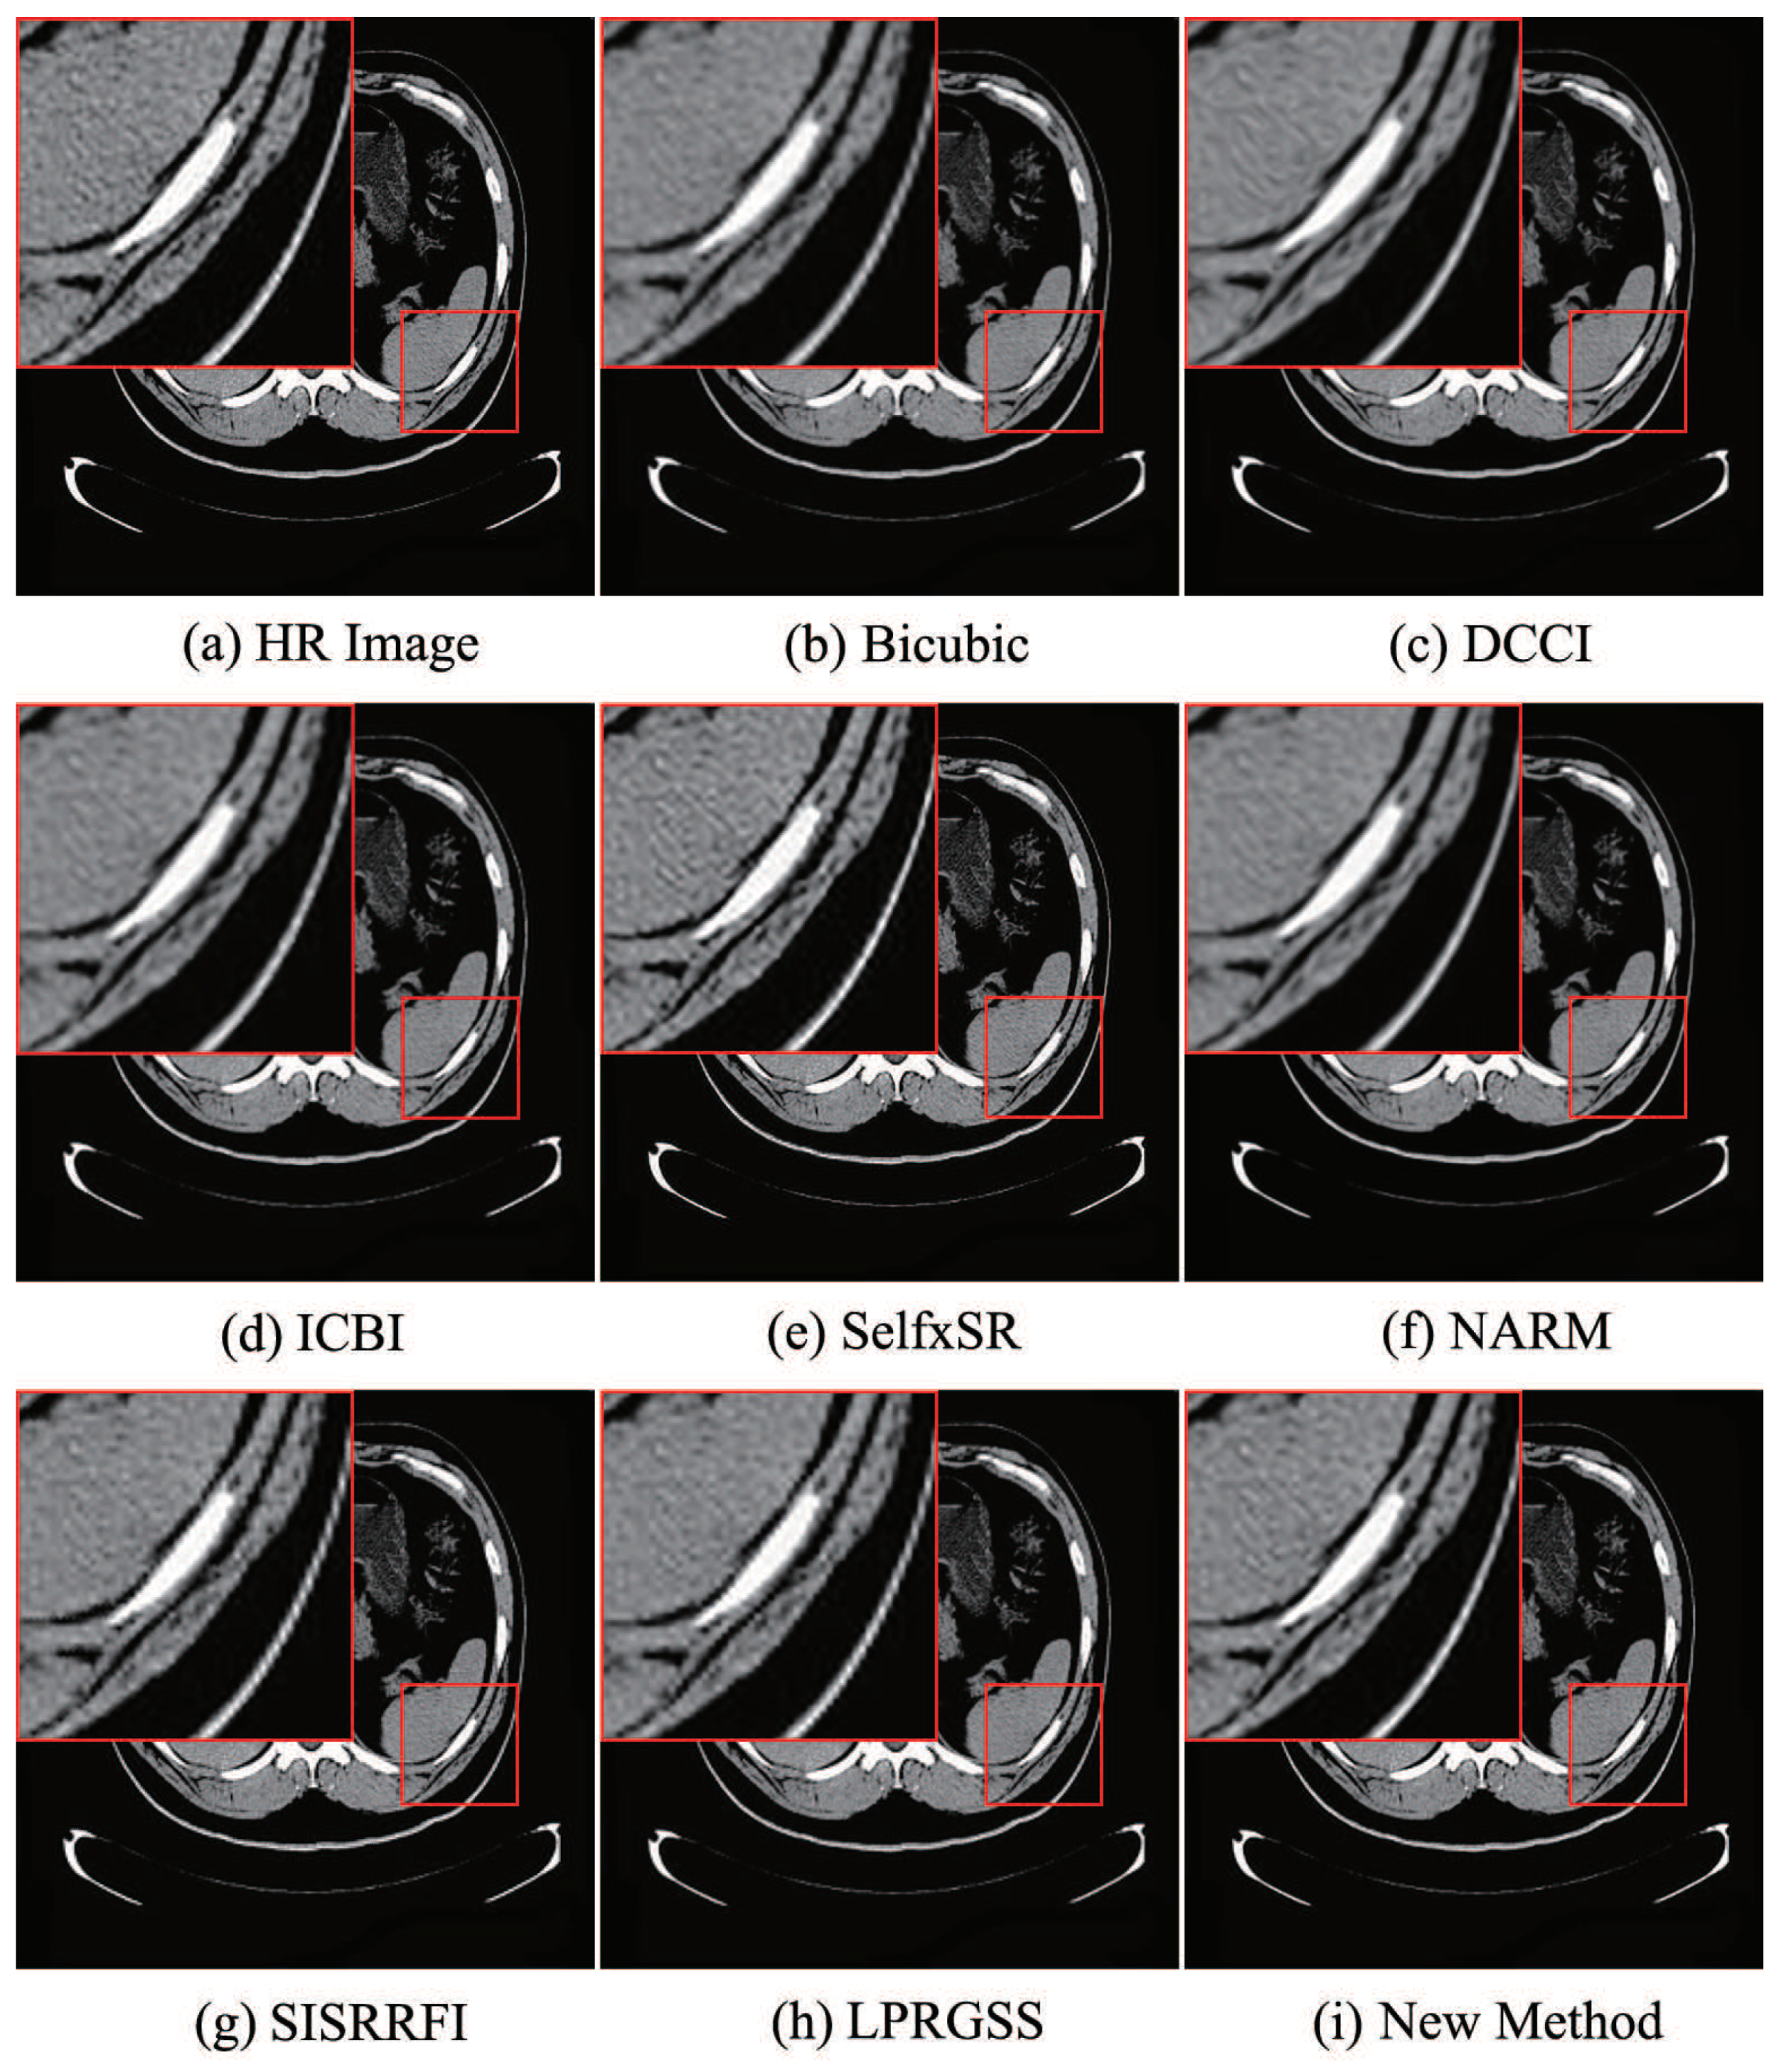

Then, we compare the visual effects of the magnified images. Experiment results show that most of the magnified images by the 8 methods have little difference in visual effects, but there are slight differences in the partially magnified images. The comparison results of visual effect of the 8 methods are given in Figure 4, Figure 5, Figure 6, Figure 7 and Figure 8, where (a) is the HR image and (b), (c), (d), (e), (f), (g), (h), and (i) are magnified images by bicubic, DCCI, ICBI, SelfxSR, NARM, SISRRFI, LPRGSS, and the new method, respectively.

In order to facilitate the comparison of visual effects, we have marked some visually distorted parts on the magnified image, as shown in the red box in Figure 4, Figure 5, Figure 6, Figure 7 and Figure 8. Figure 4 and Figure 5 show the results of the 8 methods for magnifying the two typical grayscale images. In Figure 4, it can be seen that the images (f) and (i) obtained by NARM and new method, respectively, are closest to the HR image (a); the images (c) and (d) obtained by DCCI and ICBI methods are relatively smooth at the edges and producing obvious distortion of lung tissue information; and the images (b), (g), and (h) obtained by the BiCubic, SISRRFI, and LPRGSS, respectively, have sawtooth problems at the edge. In Figure 5, the images (c), (d), and (f) obtained by DCCI, ICBI, and NARM methods, respectively, are relatively smooth at the edges, resulting in reduced detail information. The images (b), (e), (g), and (h) obtained by the bicubic, SelfxSR, SISRRFI, and LPRGSS methods, respectively, have different degrees of sawtooth problems at the edges and the edges are very rough. Overall, the image by the new method (i) is closest to the HR image (a).

Figure 4. Chest images magnified by eight methods.